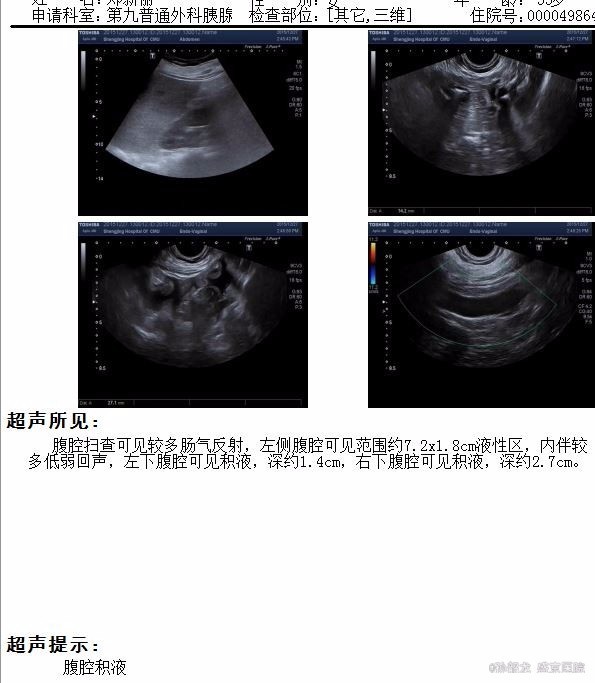

查体: 双侧乳腺缺如。腹平坦,未见胃肠型及蠕动波,腹壁无静脉曲张,左腹部可见经腹直肌切口瘢痕约20cm,以及两点状瘢痕。肝脾肋下未触及,未触及包块,全腹轻压痛,反跳痛,腹直肌紧张。Murphy’s征阴性,肝肾区无叩痛,移动性浊音阴性,肠鸣音4次/分。 辅查: 胰腺CT提示胰腺稍肿胀,轮廓模糊,胰周见模糊渗出及积液,胰腺前方腹腔内渗出。左侧肾前筋膜及邻近腹膜增厚,左侧结肠旁沟内见积液。 肝脏密度仍减低;胆囊内胆汁密度增高。扫描范围左侧胸腔积液。 腹部BUS 提示腹腔积液。 血淀粉酶和脂肪酶明显升高,血甘油三酯和胆固醇升高。

诊断: 高脂血症性胰腺炎 治疗:入院后胃肠减压,禁食水,中心静脉穿刺补液,抑制胰酶,降血脂治疗,由于腹腔有积液,彩超引导下穿刺,引出略带暗红色积液,化验积液淀粉酶,并不高,说明胰腺炎并不严重。至治疗1周左右,停用抑酶药物,复查血脂,TG降至2.62 mmol/L,引流液逐渐减少,治疗10日复查腹部彩超,几乎无积液,拔除引流管,病人腹胀痛症状明显好转,拔除胃管,清淡饮食,治疗12日顺利出院。嘱继续口服降脂药物,低脂饮食。